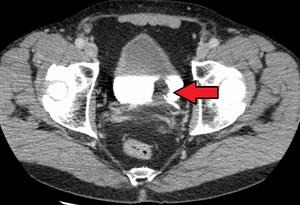

CT Urography – will detect the presence, depth and type of bladder cancer with functioning of urinary system.

Cystoscopy: – this procedure allows Uro Onco surgeon,to look inside the bladder by inserting Cystoscope through the urethra into the bladder.